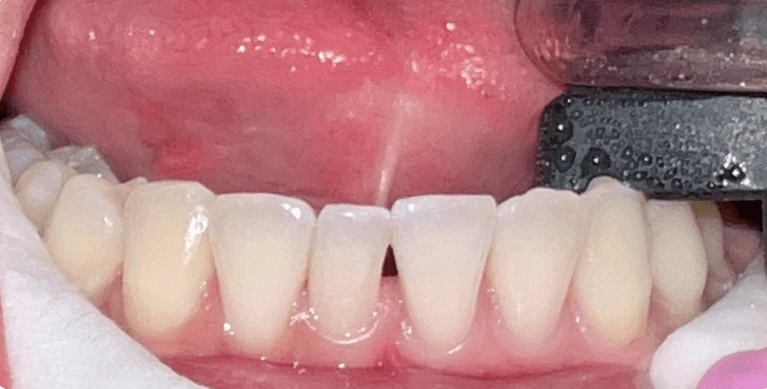

Laser gingivectomy(gum lift) to fix gummy smile and zoom whitening to lighten teeth color